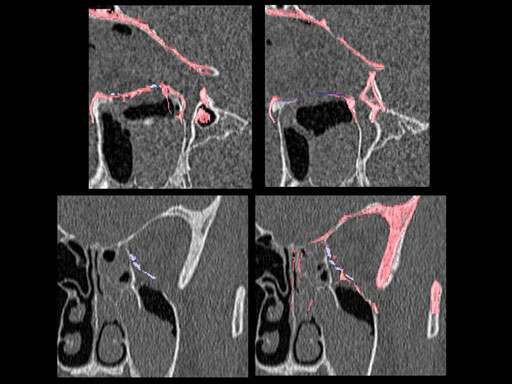

30 year old male patient with fracture of left orbital floor and medial wall.

Provided by Dr Dr Marc C Metzger, Freiburg, Germany.